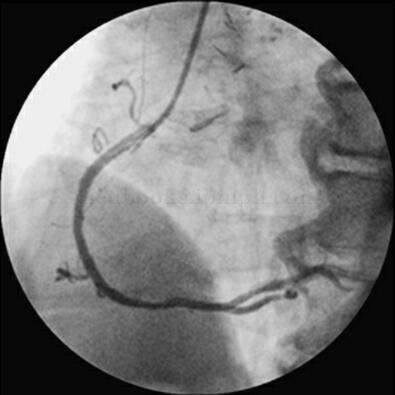

图068‐1 LAO 50°+RAO30°

1月30日冠脉造影示:左主干远段狭窄50%,LAD开口狭窄95%,中段狭窄90%,可见血栓影像;LCX开口狭窄40%,远段节段性狭窄80%;钝缘支近段狭窄70%;RCA开口狭窄70%。患者于1月31日转至胸心外科行左内乳动脉‐前降支旁路移植手术。于2月10日行RCA开口支架置入(图068‐1~图068‐5,病变处标以箭头)。